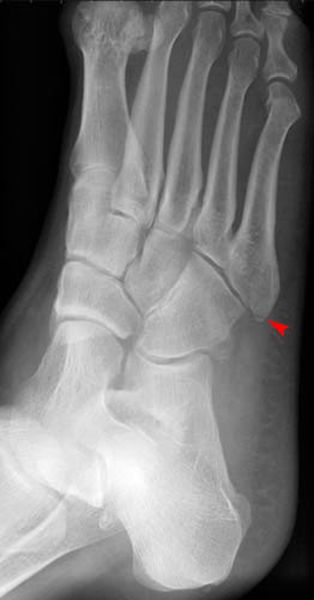

Jones Fracture

• 第五跖骨基底部骨折

• 易漏诊

• 不制动易致骨不连